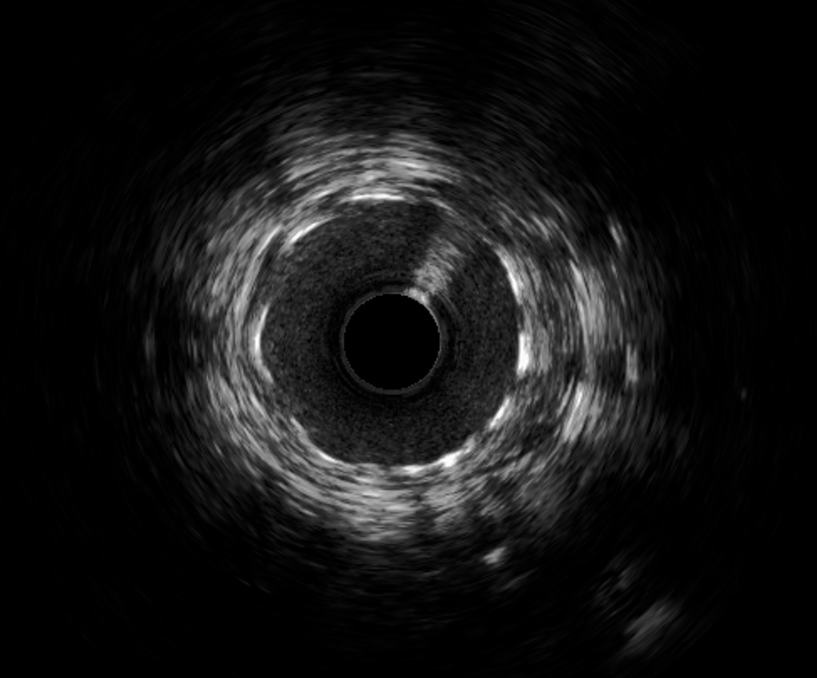

▲术前血管内超声

术前心电图同样反映出该病症的相关特征。入院后急诊冠脉造影发现,前降支近段存在50%局限性狭窄,中段节段性病变,且最重狭窄达到90%并可见明显的血栓影。为更精准把握血管内部情况,我院团队进一步行血管内超声检查,结果显示前降支中段可见纤维脂质斑块,最小管腔面积仅为2.11mm²,斑块负荷高达81.5%。面对如此复杂的病情,我院介入团队沉着冷静、有条不紊地开展救治工作,先进行球囊扩张,而后成功植入一枚3.0*30mm支架。术后再次通过血管内超声检查确认,支架贴壁、膨胀良好,最小管腔面积已提升至6.15mm²,手术结果十分满意,患者胸痛症状明显缓解。